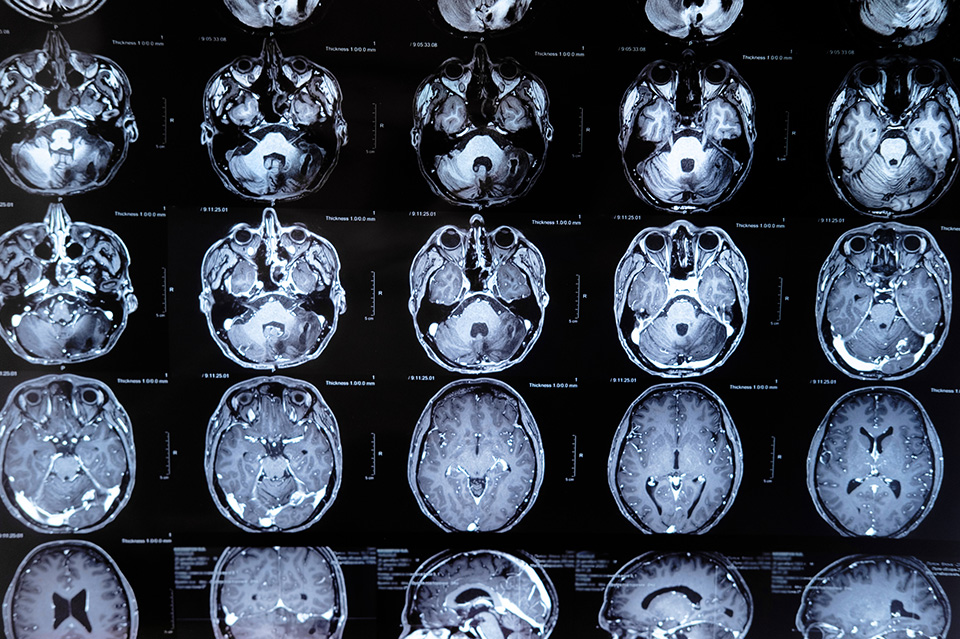

- 画像診断…X線やCTスキャン、MRI、PETスキャン等の画像検査が、がんの位置や進行度を調べるのに役立ちます。